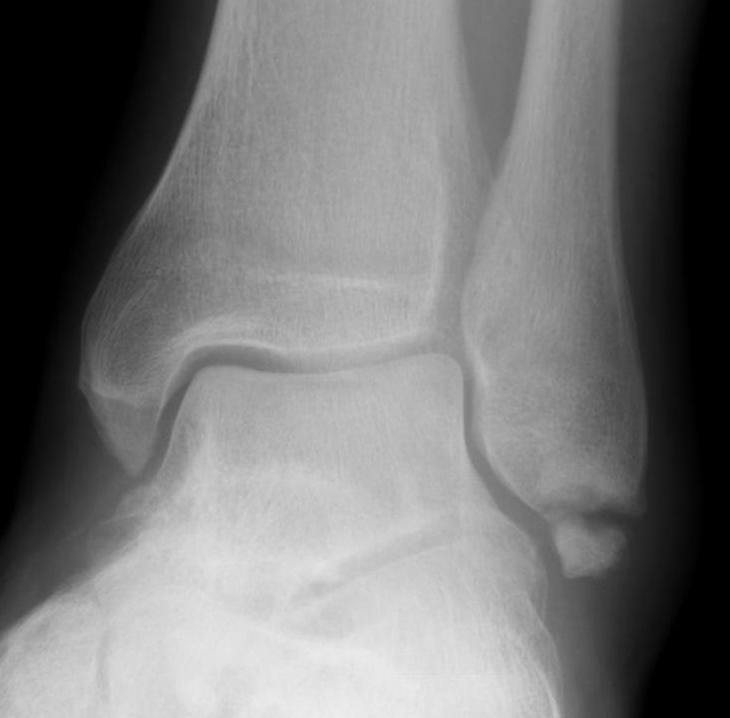

X-ray assessment

3 standard views

AP / Lateral / Mortise

Mortise

- AP with foot internally rotated

- should be symmetrical space around talus

Ankle Mortise ViewMortise

Increased tibio-fibular clear space  Overlap Increased medial clear space

Medial border of the fibula

Lateral border of the posterior tibia (incisura fibularis)

Measured 1 cm above the plafond

Overlap of the fibula and the anterior tibial tubercle

Medial talus to lateral medial malleolus

<5mm AP and mortise

> 6 mm AP view

> 1 mm mortise view

< 4mm

Equal to superior clear space